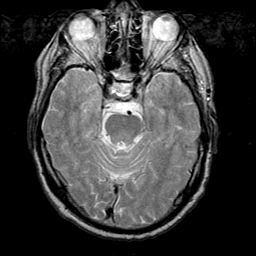

Meningioma, MR Study #1 -- Slice #6

[Home][Help][Clinical] Slice 6